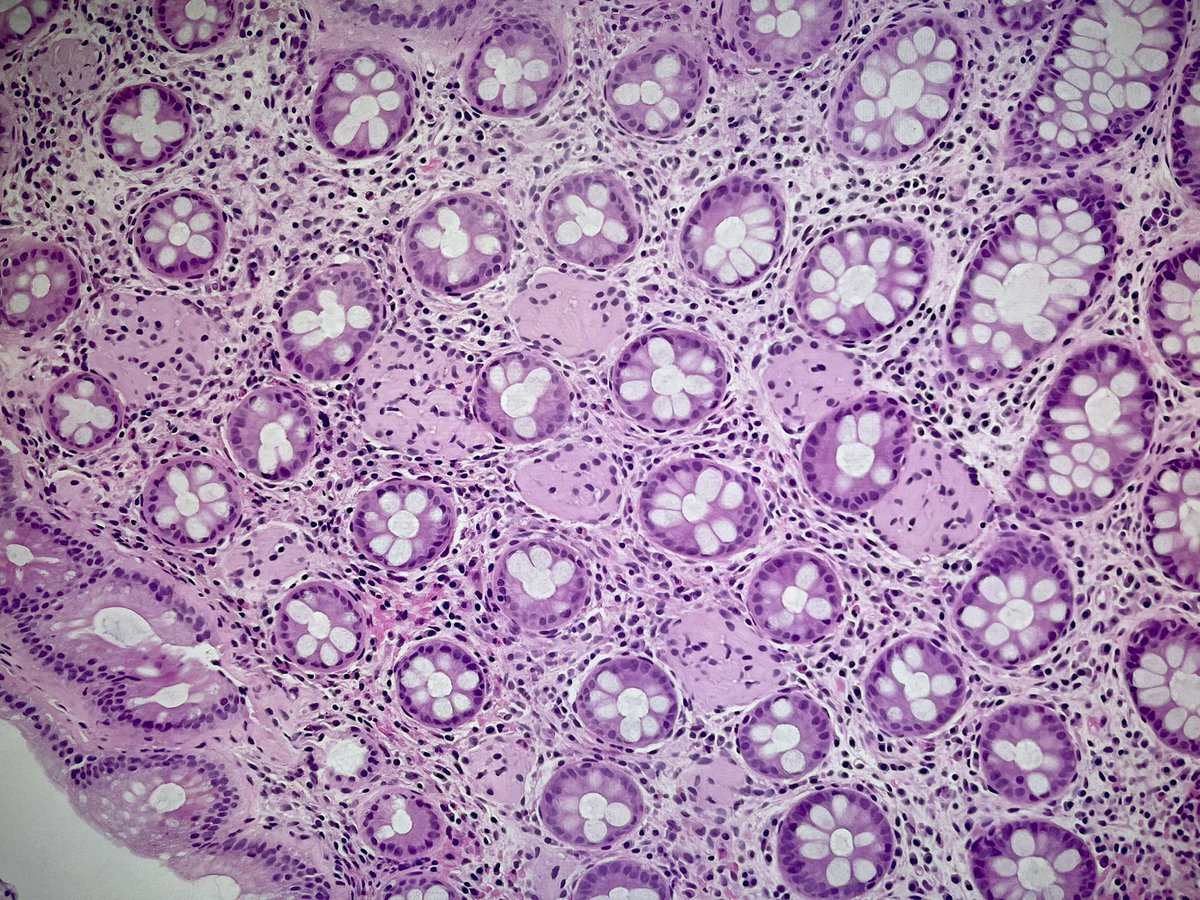

A teaching point from our Editors. How do you distinguish between intrapancreatic bile duct carcinoma and pancreatic ductal carcinoma? Samuel Freire